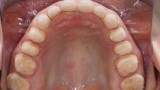

W pierwszym etapie diagnostycznym wykonano zdjęcia zewnątrz- i wewnątrzustne (ryc. 1-12).

Wykonano także modele diagnostyczne zaartykulowane w relacji centralnej (RC), którą zarejestrowano ze względu na zwiększone napięcie mięśniowe z wykorzystaniem deprogramatora Koisa (ryc. 13-15), oraz zdjęcie pantomograficzne (ryc. 16) i cefalometryczne. Analiza modeli w RC wykazała przesunięcie żuchwy w kierunku doprzednim w stosunku do pozycji maksymalnego zaguzkowania i przedwczesne kontakty funkcjonalne na zębach bocznych, co tłumaczyło obecność odprysków szkliwa na brzegach siecznych górnych zębów (szczególnie wyraźne na zębie 12) (ryc. 14, 17). Na modelach wykonano studium funkcjonalne mające na celu określenie, w jaki sposób można odtworzyć prawidłową funkcję, tzn. uzyskać prawidłowy nagryz pionowy i poziomy oraz prowadzenie przednie (ryc. 18-20).